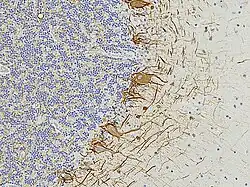

A formalin fixed and paraffin embedded section of human cerebellum stained with an antibody to neurofilament light, NF-L revealed with a brown dye, cell nuclei are revealed with a blue dye. Nuclear rich region at left is granular layer, region at right is molecular layer. The antibody binds processes of basket cells, parallel fiber axons, the perikarya of Purkinje cells and various other axons.